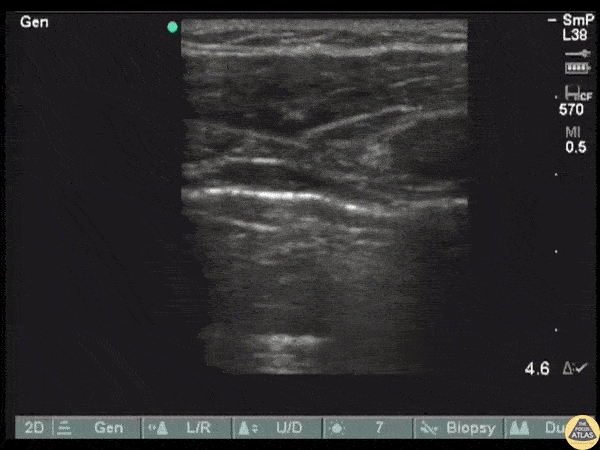

Initially, this clip reveals a lack of pleural sliding in a patient with a pneumothorax. POCUS was used to reveals the return of lung sliding as the visceral and parietal pleura approximate following chest tube insertion. Image courtesy of Robert Jones DO, FACEP @RJonesSonoEM Director, Emergency Ultrasound; MetroHealth Medical Center; Professor, Case Western Reserve Medical School, Cleveland, OH View his original post here